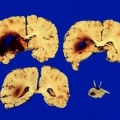

Клиническая картина зависит от локализации кровоизлияния и заключается в возникновении параличей и парезов на противоположной стороне тела, нарушении речи и движения глазных яблок, зрения, нарушения чувствительности, что сочетается, как правило, с общемозговой симптоматикой (головная боль, тошнота, рвота, внезапное угнетение или утрата сознания), которые сохраняются более 24 часов.

При кровоизлиянии в мост – отдел ствола мозга – отмечается раннее развитие комы. Кровоизлияния в мозжечок характеризуются внезапным головокружением и рвотой в сочетании с выраженными нарушениями походки и устойчивости позы.

При кровоизлиянии в мозг летальный исход в первый месяц наблюдается у 40 – 60% больных. Смертность в течение года после инсульта составляет 50-65% в зависимости от локализации и размеров кровоизлияния. Около 60-80% перенесших внутримозговое кровоизлияние больных имеют функциональные неврологические нарушения разной степени выраженности.

Осложнения: гематома (скопление крови), отек мозга, тромбоэмболия легочной артерии, пневмония (воспаление легких), инфаркт миокарда, сердечная недостаточность